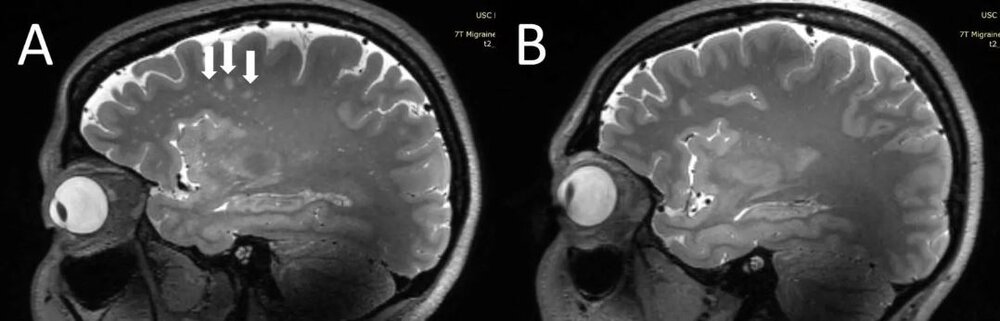

ژو و همکارانش، به دنبال آن هستند تا ارتباط میان میگرن وبزرگ شدن فضاهای اطراف عروقی را درک کند. این محققان با بهره‌گیری از MRI ۷T با وضوح فوق‌العاده بالا، به مقایسه ساختاری تغییرات میکروواسکولار (رگ‌های خونی بسیار ریز) در انواع مختلف میگرن پرداختند. ژو در این رابطه گفت:« این اولین بررسی با استفاده از MRI با وضوح فوق‌العاده بالاست که در آن به بررسی تغییرات میکرو واسکولار مغز در پی بروز میگرن، به‌ویژه در فضاهای اطراف عروقی پرداخته می‌شود. از آنجا که MRI ۷T قادر است تا تصاویری با وضوح و با کیفیت به مراتب بالاتری نسبت به دیگر دستگاه‌های MRI از مغز ارائه دهد، می‌توان از این دستگاه برای تشخیص تغییرات جزئی‌تر و ریزتری که بعد از بروز میگرن در بافت مغز ایجاد می‌شود، بهره برد.»

تجزیه و تحلیل‌های آماری حکایت از آن داشت که تعداد فضاهای بزرگ شده اطراف عروقی در مرکز سِمی اوال مغز افراد، در بیمارانی که میگرن داشتند، به مراتب بیشتر از افراد سالم بود. به علاوه کمیت فضاهای بزرگ شده اطراف عروقی در مرکز سِمی اوال با عمق ماده سفید، از نظر شدت جدی بودن در بیماران میگرنی در ارتباط است.

ژو ادامه داد:« ما در تحقیقات درباره میگرن مزمن و میگرن اپیزودیک بدون هاله به این نتیجه رسیدیم که در هر دو دسته افراد مبتلا به این نوع میگرن‌ها، فضاهای اطراف عروقی در مرکز سِمی اوال بزرگتر بودند. اگرچه ما هیچ تغییر قابل توجهی در شدت ضایعات بخش سفید مغز در افراد مبتلا به میگرن و افراد بدون میگرن پیدا نکردیم، ولی این ضایعات بخش سفید مغز به طور قابل توجهی با وجود فضاهای بزرگ شده اطراف عروقی مرتبط بودند. این بدان معناست که تغییرات در فضای اطراف عروقی، ممکن است منجر به افزایش ضایعات بیشتری در بخش سفید مغز شوند.»